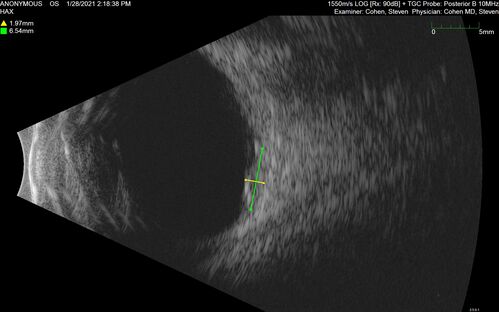

Bilateral Choroidal Tumors - Metastatic Breast Cancer

51 year old female.  First 3 sets of images show lesions growing despite systemic chemotherapy.  She eventually had external beam radiation x 15 sessions and the tumors shrunk in the last two sets of images